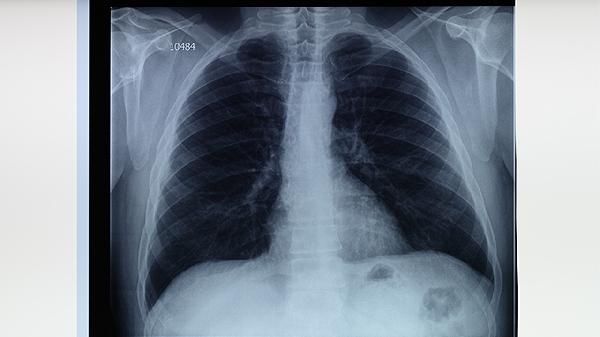

肺结核患者经规范抗结核治疗后,痰涂片检查连续多次阴性可判定为无传染性,但病灶中仍可能存在处于休眠状态的结核菌。此时若擅自停药,残留细菌可能重新活跃导致病情反复,甚至发展为耐多药结核病。标准短程化疗方案通常需6-9个月,强化期使用异烟肼片、利福平胶囊、吡嗪酰胺片、乙胺丁醇片四联用药,巩固期减少为异烟肼片和利福平胶囊。治疗期间需定期复查胸部CT和痰培养,由医生评估是否调整用药。部分患者病灶吸收缓慢或存在肺外结核,可能需要延长疗程至12个月。